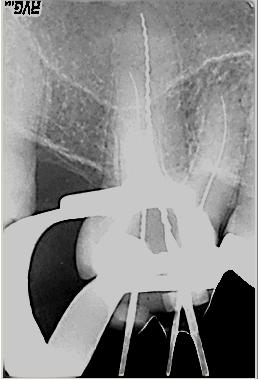

Röntgenologischer Ausgangsbefund im Febr. 2003 mit caries profunda, starken Krümmungen sowohl der mesiobuccalen wie auch der distobuccalen Wurzeln

Zustand unmittelbar vor Behandlungsbeginn im Juni 2003. Die Fraktur des distalen Zahnanteils hat die Patientin jetzt zur Einwilligung in die Behandlung motiviert. Auffällig ist in dieser Projektion die besonders starke Krümmung der mb Wurzel sowie die knochennahe Defektlage distal. Es erfolgte zunächst die Kariesentfernung gefolgt von einer chirurgischen Kronenverlängerung zur Herstellung der biologischen Breite sowie Ermöglichung des sog. Ferrule-Effektes. Danach wurde der Zahn adhäsiv aufgebaut. Erst jetzt wurde mit der eigentlichen WKB begonnen